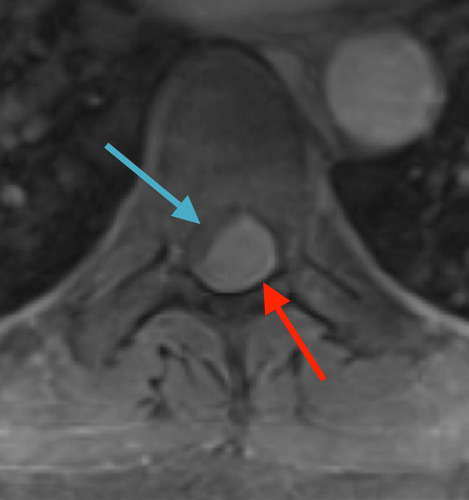

Preoperative MRI T1w demonstrating a large enhancing tumor (red arrow) causing severe cord compression and displacement (blue arrow)

Preoperative MRI T1w demonstrating a large enhancing tumor with severe cord compression